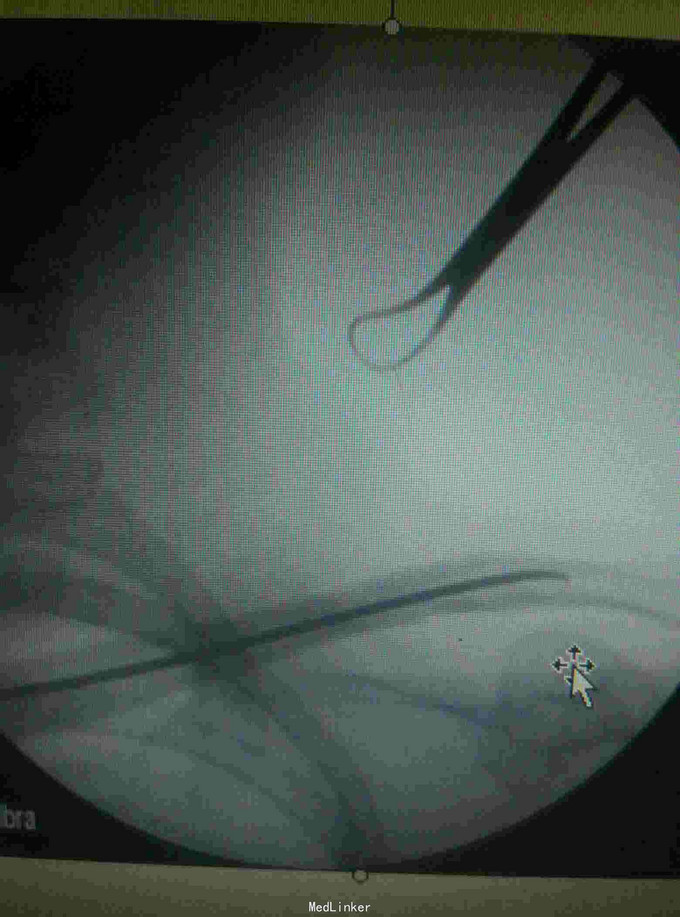

诊断:左锁骨骨折, 治疗:闭合复位TEN固定术

术后恢复良好,术后4个月拔除TEN 讨论:大部分锁骨骨折可以通过闭合复位钢针固定,但如果是骨质疏松病人,容易出现松动或退针等可能。而TEN更具有抗弯曲稳定,抗旋转稳定,横向稳定,轴向稳定,所以骨质比较疏松患者,我们采用TEN进行固定。